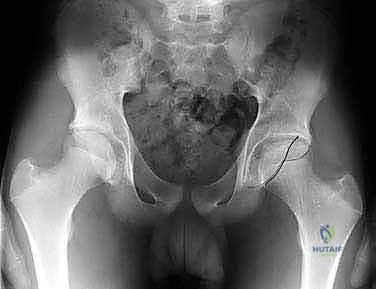

- التصوير بالأشعة السينية (X-rays): صور دقيقة بوضعيات خاصة (AP Pelvis, Dunn view, Cross-table lateral) لقياس زوايا محددة مثل زاوية ألفا (Alpha Angle) التي تؤكد وجود تشوه "كام"، وعلامة التقاطع (Crossover Sign) التي تؤكد وجود تشوه "بنسر".

صورة شعاعية قبل التدخل الجراحي توضح التشوه العظمي بوضوح.